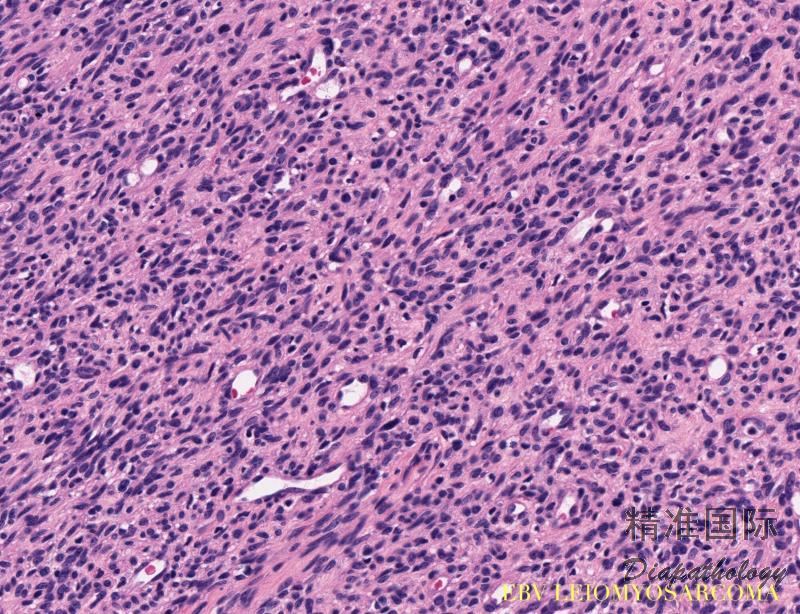

- 镜下见肿瘤由成束的梭形细胞组成,可呈交织状排列,从典型的平滑肌肉瘤到分化成熟的平滑肌细胞,瘤细胞异型性不显著,瘤细胞核分裂活跃,瘤组织见较多的淋巴细胞浸润(主要为 T 淋巴细胞);